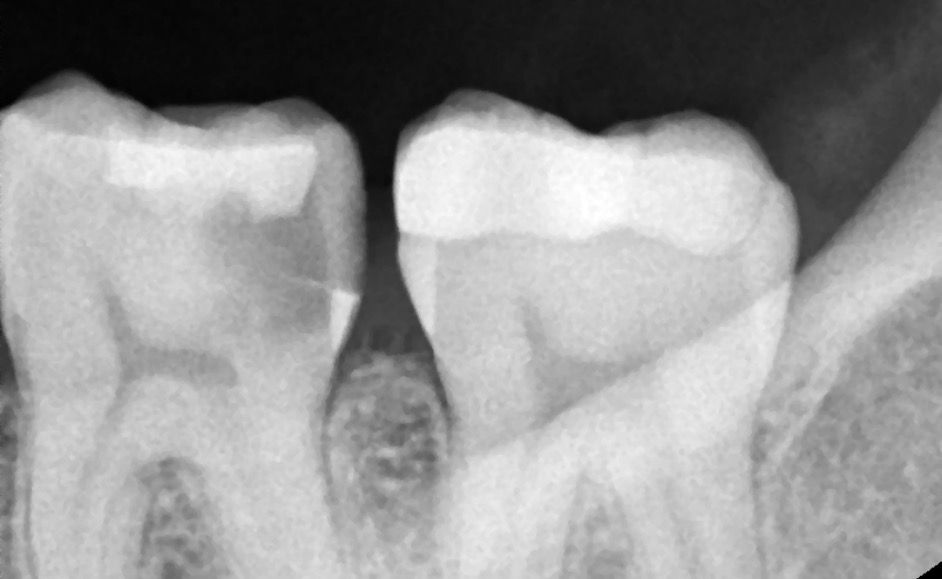

치과에서 신경치료 해야한다는데 이정도면 어떤 상태인건가요??

사진상에 보이는 치아는 신경치료를 하셔야될것같습니다. 치아 뒷면이 많이 썩어 잇는거 같습니다.

사진에는 인접면에 충치가 크게 생긴것으로 보입니다. 이정도의 충치라면 대부분 신경치료를 하게 됩니다

신경치료를 하게 되면 치아를 씌우는 크라운 치료를 받게 됩니다.

첫번째 큰 어금니 충치 내지는 파절이 치아 속 신경과 근접해보입니다 신경치료가 필요할 것 같습니다.